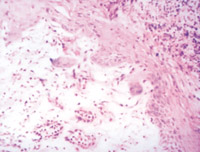

5-2-1 伤后第1天,表皮凝固性坏死,真皮浅层胶原纤维变性 HE×100